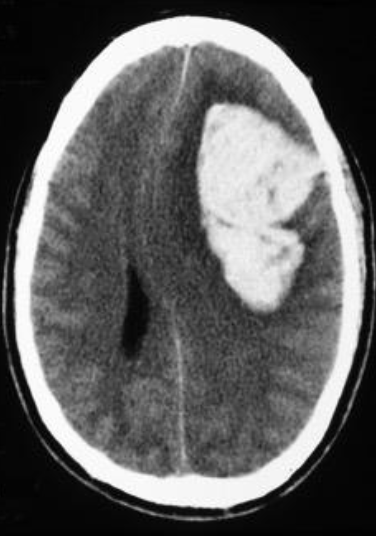

Hx: previously healthy 20 yo with new onset seizures Epi: lifelong exposure in a rural area with poor sanitation & extensive contact with pigs PE: unremarkable Dx? Ix? Rx?

Neurocysticercosis CT B T. solium Western Blot (+). Rx: Albendazole + PZQ X 10d. Dexamethasone starting 2 days before +/-Antiepileptic